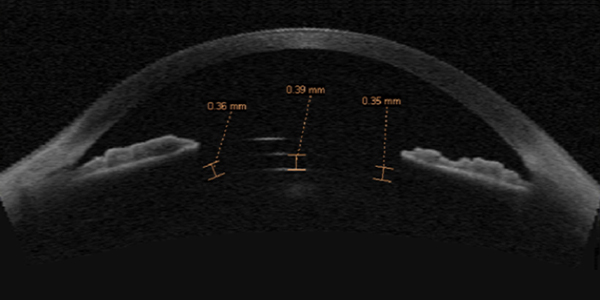

후방렌즈 ICL의 안전한 볼팅(Vaulting) 기준에 대하여

ICL 렌즈삽입술 전후 각막 전안부 CT